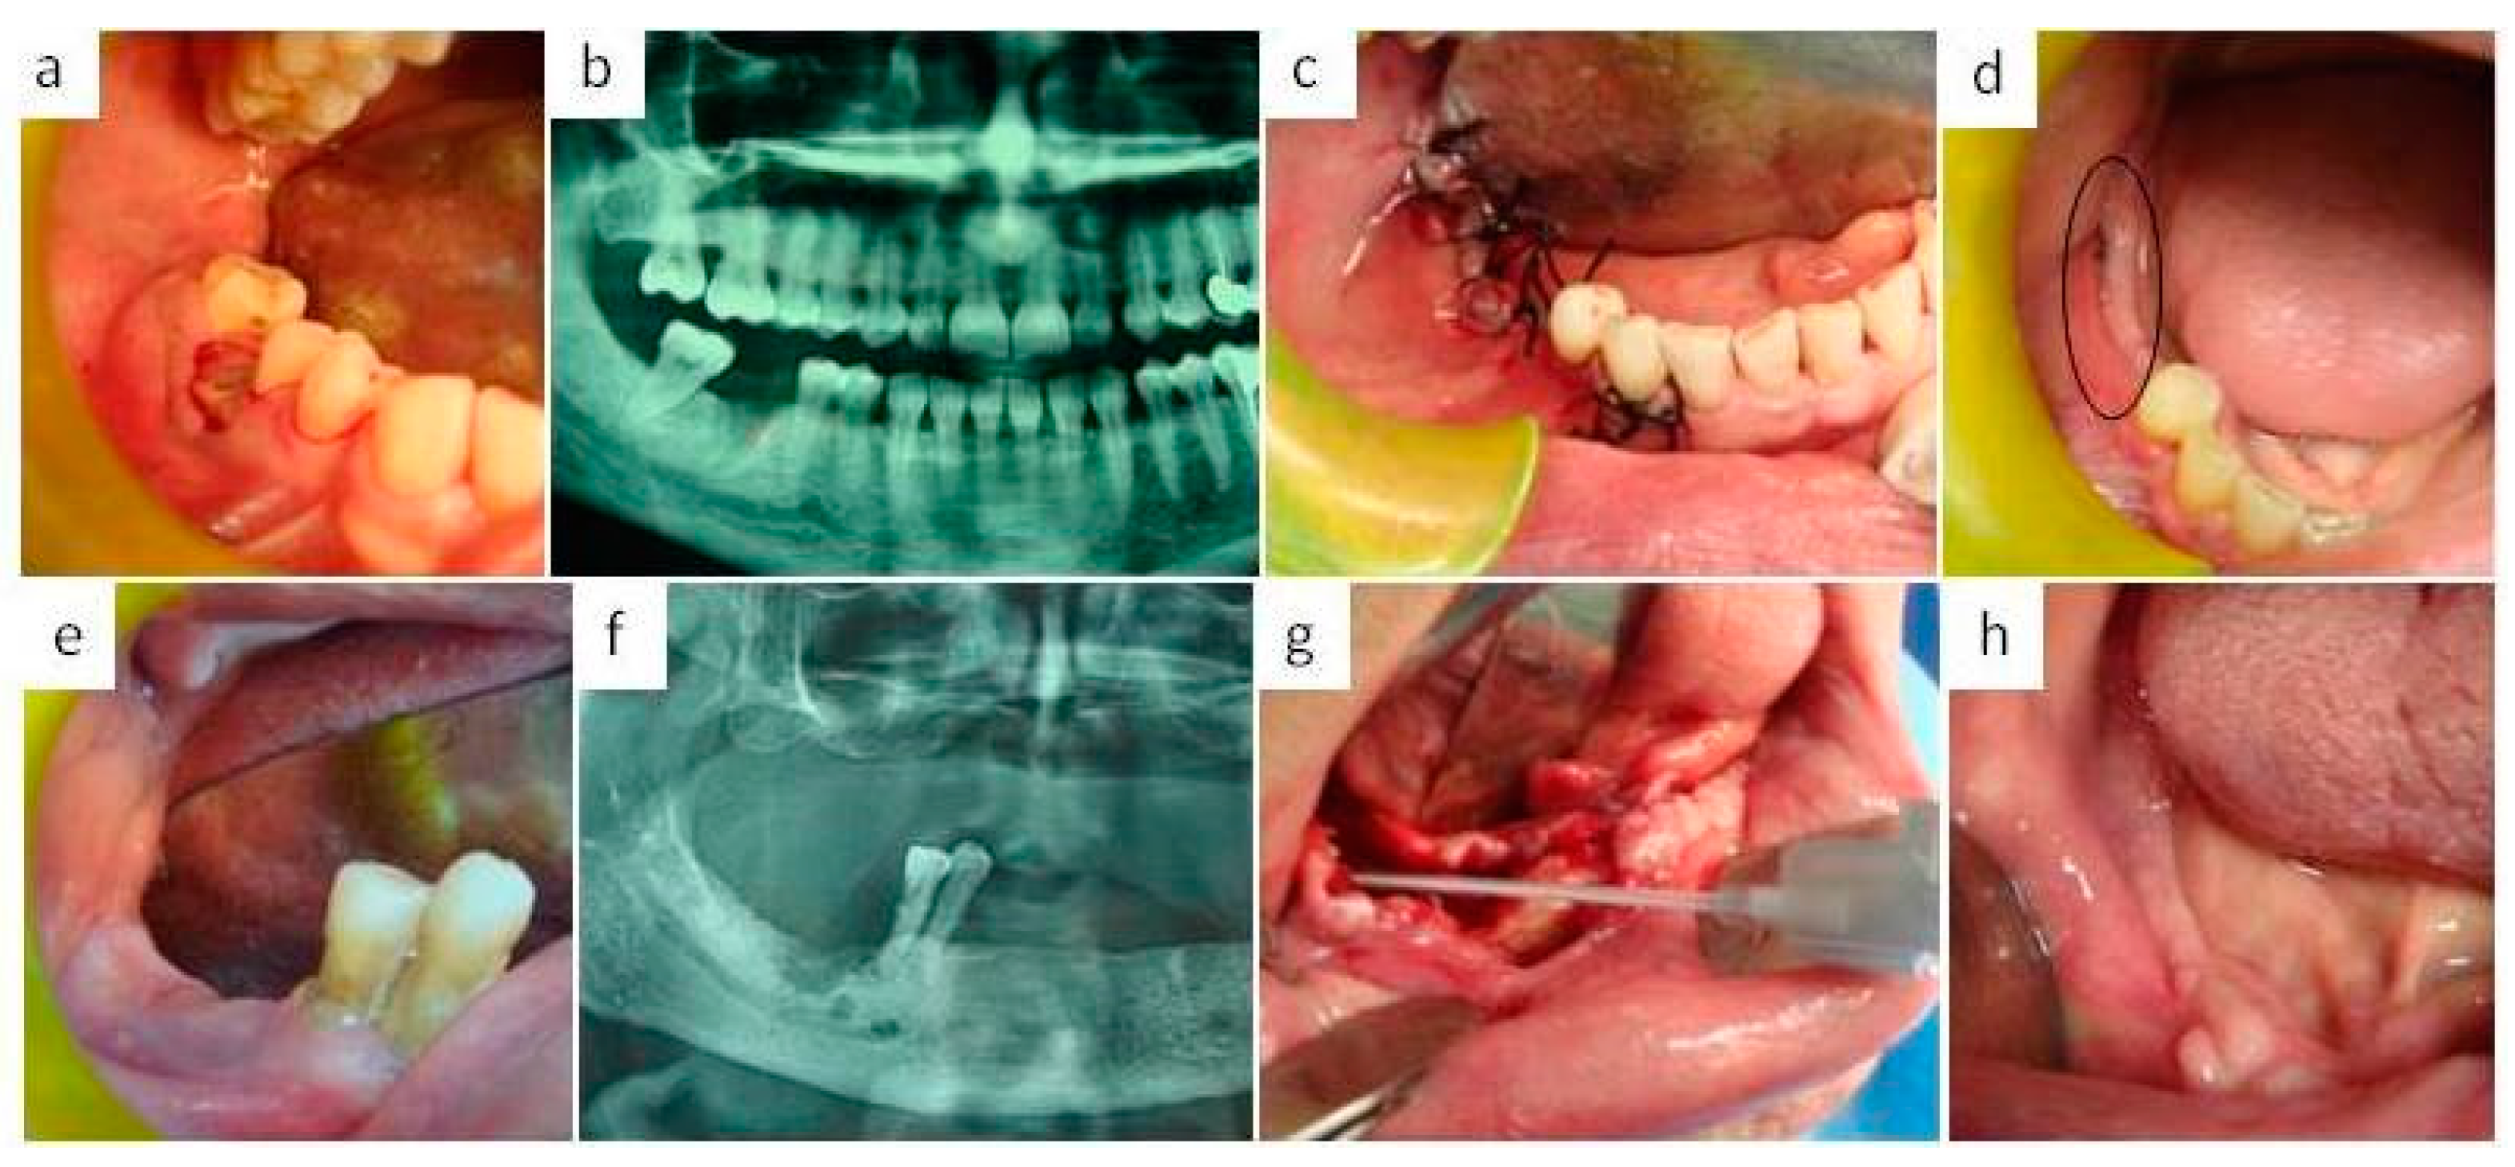

2. Material and Methods

- Group A patients

- Group B patients

- Group C patients

- Group D patients

- Group E patients

- Group F patients

- Group G patients